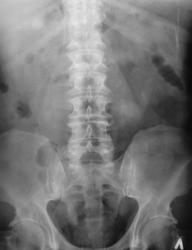

Пациент с диагнозом "МКБ" направлен на обзорную рентгенографию почек и мочевыводящих путей.

Пациент с диагнозом "МКБ" направлен на обзорную рентгенографию

Внутривенная урография.

На мой взгляд дополнительная интенсивная тень лежит за контуром почки. В проекции Желчного пузыря. Так что желчекаменная болезнь? Рекомендованно УЗИ печени и желчного пузыря.

Да с камнем желчного то все понятно...но вот тень в проекции н\трети правого мочеточника ....весьма необычна...вопрос - куда ее "пристроить"?))))

Да, камешек для желчного типичный.

А тень в дистальной трети мочеточника действительно "фердиперсовая"...

Вы правы, камней не много, их - до "фига"...